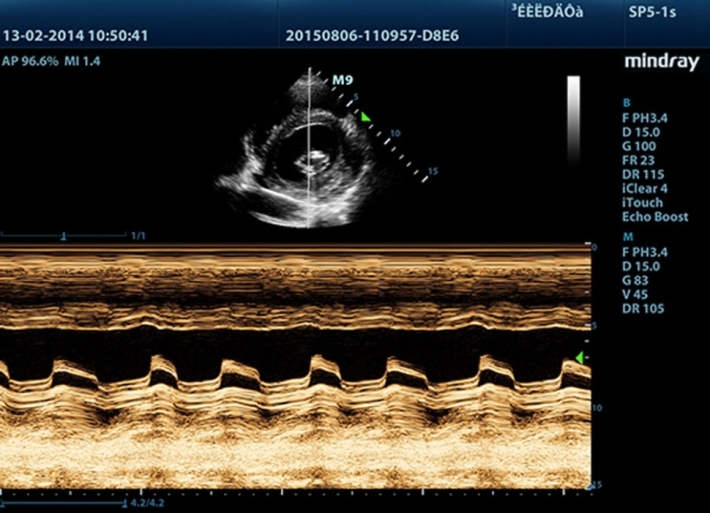

Медицинское оборудование и сервисное обслуживание